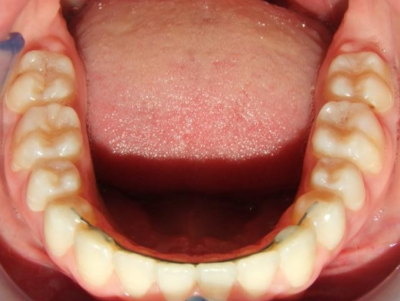

Behandeling Heleen

eindfoto

7-13 Twin Block

14-26 volledig vast boven- en onderkaak + TPA